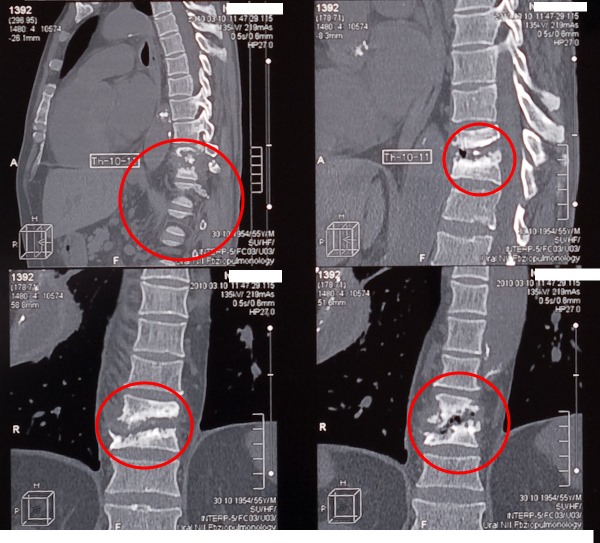

Компьютерная томография (КТ) позвоночника при туберкулезе

Для более детального изучения развития заболевания применяются и другие диагностические методы, такие как: ультразвуковое исследование (УЗИ); компьютерная томография (КТ); гистологическое исследование тканей пораженного участка; биопсия.